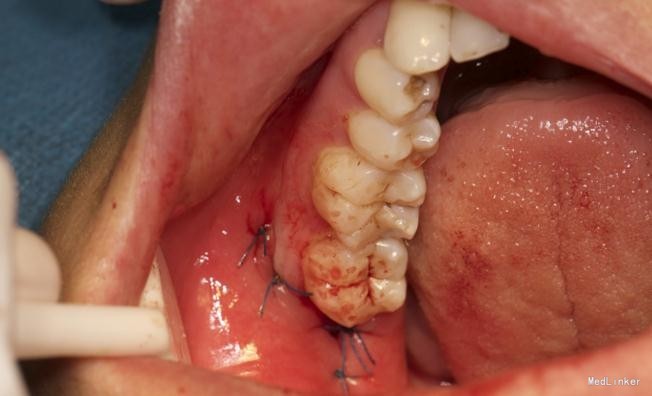

效果很好,患者满意

挺好的且较常见的病例,最主要的是照片很清晰!在拔出了阻生齿后,患者的对颌牙是不是应该同时或者择日拔除呢,对颌牙伸长很快的……

详尽的病例,值得学习。水平阻生的智齿应该尽早拔除,以免后患,极容易在7和8之间形成食物嵌塞而导致7的远中邻面龋坏。8远中的盲袋也易导致冠周炎